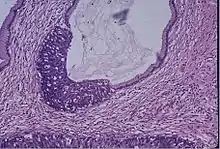

Breast cancer screening is the medical screening of asymptomatic, apparently healthy women for breast cancer in an attempt to achieve an earlier diagnosis. The goal of early detection is to find the cancer when it is treatable. A number of screening tests have been employed, including clinical and self breast exams, mammography, clinical breast exam, breast self-exam, thermography, tissue sampling and magnetic resonance imaging. Mammography is the method most commonly used for breast cancer screening for women who are 50 years and older. There are 3D mammograms now in use and for women who are at higher risk for breast cancer they can have an MRI.[23]